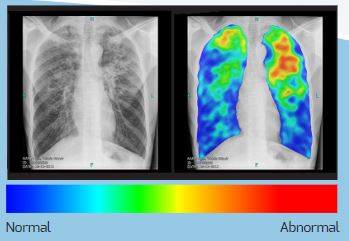

Le boîtier hors ligne CAD4TB est connecté à des systèmes radiologiques numériques validés pour recevoir des images radiologiques thoraciques postérieures - antérieures (PA). Le logiciel installé sur le boîtier analyse la radiographie du thorax en moins d'une minute. Le résultat est une carte thermique en couleur montrant les anomalies suspectes liées à la tuberculose, et un score entre 0 et 100 représentant la probabilité globale de tuberculose. Un score seuil est choisi pour déterminer quels patients doivent être orientés vers un test de suivi, tel que le GeneXpert, pour confirmer le diagnostic de TB. CAD4TB ne fournit pas d'informations sur les diagnostics non tuberculeux, dans de nombreuses situations, des lecteurs humains sont encore nécessaires pour examiner les radiographies pulmonaires.

Image